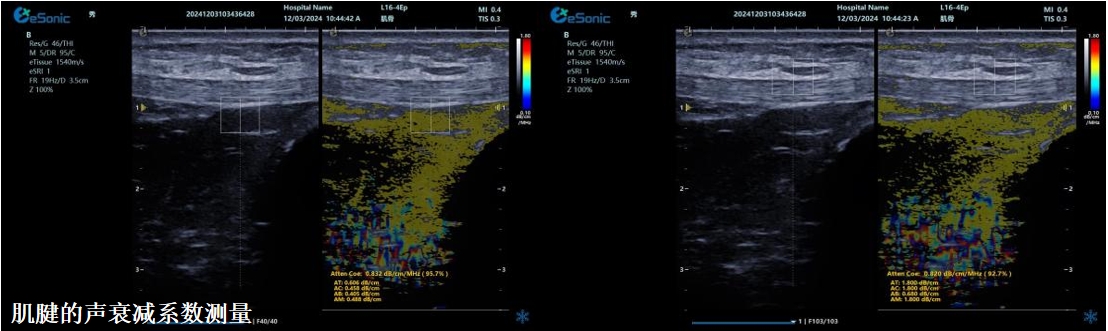

ATI高级声衰减成像

?独有的幅度损失的衰减方法ALA,准确性高,稳定性好,实时性好?业界唯一支持凸阵与线阵两种探头?支持多个取样框?提供两种显示单位

1b93bd09b343ed7a1e0b155407e34f4.png

肌骨领域的应用

?肌腱炎症或损伤的评估?肌肉拉伤的定位?关节磨损或炎症的诊断?骨质疏松的早期发现和监测

c8236a86e68d65834436e5fdd9b2629.png